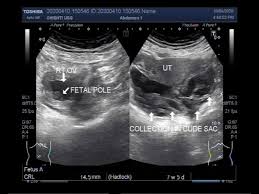

It’s important to understand that fluid in the cul-de-sac during early pregnancy doesn’t automatically mean an ectopic pregnancy. While it can be a sign, other factors need to be considered. For example, hCG levels that aren’t rising as expected and an ultrasound that can’t pinpoint the pregnancy location might point towards an ectopic pregnancy. In such cases, procedures like dilation and curettage (D&C) or manual vacuum aspiration (MVA) might be recommended. These procedures can help determine if a gestational sac or chorionic villi are present, which can offer more definitive information.

However, cul-de-sac fluid can also occur due to other reasons, such as a normal pregnancy or fluid buildup from a prior surgery. Therefore, it’s crucial to consult with a healthcare professional who can assess your specific situation. They will consider all factors, including your medical history, symptoms, and test results, to arrive at an accurate diagnosis and guide your care.

It’s crucial to remember that an ectopic pregnancy occurs when a fertilized egg implants outside the uterus, typically in the fallopian tube. This is a serious medical condition that requires immediate attention. If you’re experiencing any of these symptoms, seek medical care immediately.

Ultrasound Video Showing Ovarian Pregnancy And Free Fluid In Cul De Sac.